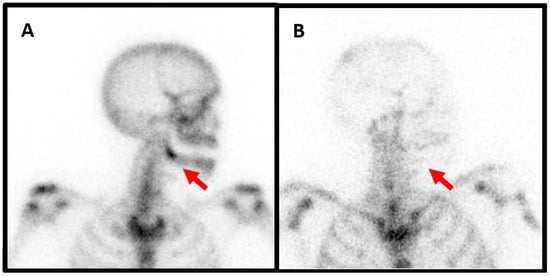

Figure 4. Planar scintigraphy imaging of a 67-year-old patient who had the extraction of tooth 38 with transient improvement. A few months later, the same pain recurred and was difficult to control with multiple analgesic attempts. Biological results showed no infectious signs. The anterior planar image acquired 6 h after the intravenous injection of anti-granulocyte antibodies showed no radiotracer uptake in the left mandibula ((A), red arrow). Likewise, no radiotracer uptake was seen in the left mandibula on the anterior left profile image acquired 24 h after the radiopharmaceutical injection ((B), red arrow). The blood pool phase (anterior view) of the bone scan showed no left mandibular hyperemia ((C), red arrow). On the other hand, the delayed image of the bone scan (anterior view) showed marked radiotracer uptake ((D), red arrow).

Figure 5. Single-photon emission computed tomography (SPECT), computed tomography (CT) and fusion images of the same patient showed no anti-granulocyte antibody uptake in the left mandibula ((A), red and white arrows). The images of the CT scan showed reactive osteosclerosis with no lytic or soft tissue collection suspicious of active infection (middle image, red and white arrow). The bone scan SPECT/CT showed intense radiotracer uptake in the left mandibula ((B), red and white arrows), indicating active osteoblastic activity. The patient was treated us biphosphonates and a follow-up bone scan SPECT/CT was repeated two years later, which showed a marked decrease in left mandibular radiotracer uptake ((C), red and white arrows).